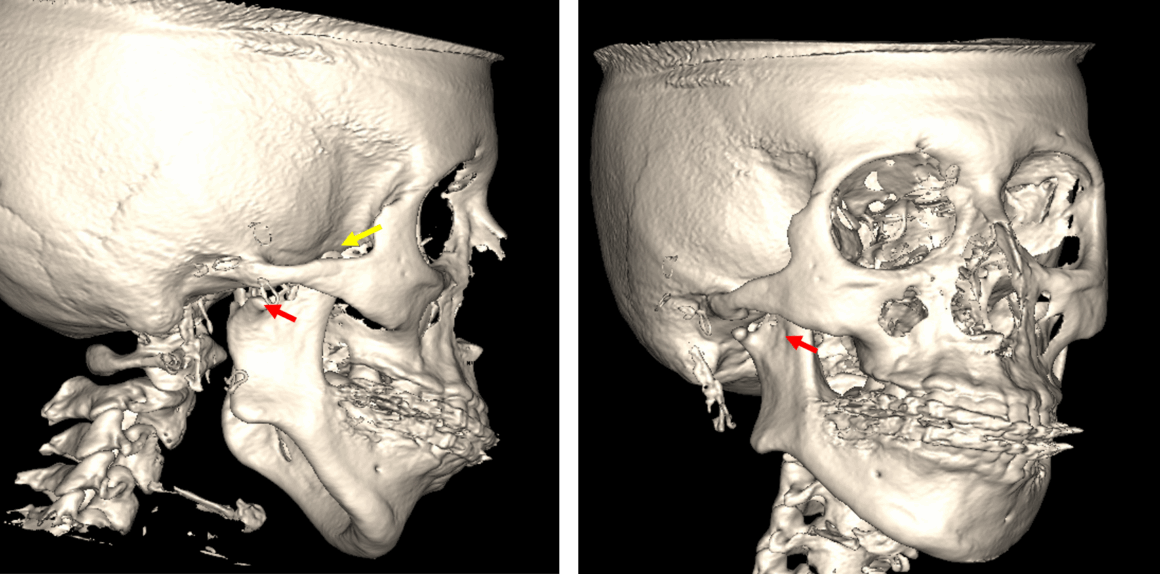

Fig.1

En la evaluación con tomografía computarizada cone beam, se realizó la reconstrucción panorámica del maxilar superior (Fig.1) donde se observa la aparente ausencia del cóndilo mandibular del cóndilo mandibular derecho, así como el elongamiento de la apófisis coronoides, la acentuación de la escotadura antegonial y la disminución en el tamaño de la rama ascendente mandibular.